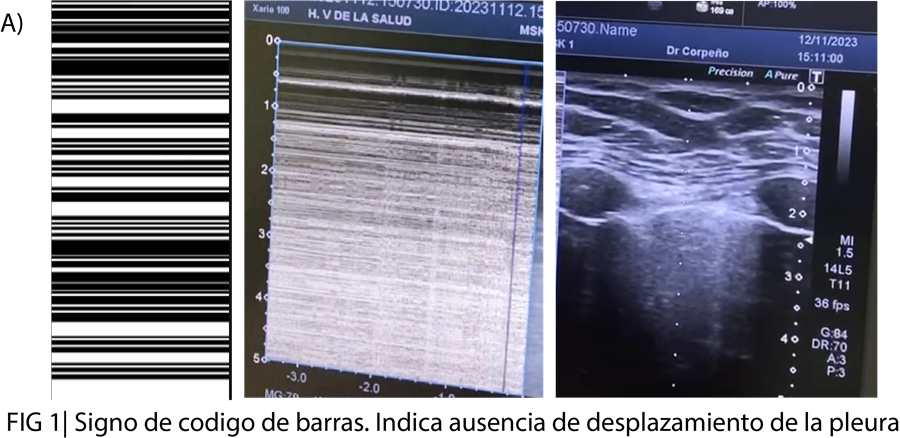

Se trata de una mujer de 46 años que acude por presentar contusión costal izquierda tras caída fortuita de madrugada acude a urgencias 10 horas después de la caída refiriendo dolor costal, no disnea. Exploración Física TAS: 140,0 TAD: 95,0 FC: 95 FR: 22 Saturación de Oxígeno: 97 no IY. TORAX: Dolor a punta de dedo anterolateral izquierdo, no crepitación, no enfisema subcutáneo, MVC disminuido en posterior y lateral. Se realiza ecografía clínica a pie de cama observando líneas A, no líneas B, no deslizamiento pleural con signo de código de barras, ausencia de pulso pulmón. Se realiza Rx de parilla costal y tórax: Fractura de 6 arco costal izquierdo y neumotórax izquierdo.

Se trata de una mujer de 46 años con dolor costal, sin disnea, ni repercusión ventilatoria al momento de su llegada pero que mediante ecografía a pie de cama se reveló un neumotórax oculto (signo de código de barras). La paciente requirió drenaje torácico ecoasistido logrando expansión pulmonar.

En este caso, la ecografía clínica permitió identificar hallazgos clave: ausencia de deslizamiento pleural, presencia de líneas B, signo de código de barras y ausencia de pulso pulmón. Aunque no se observó el pulso pulmón, que tiene menor sensibilidad, se confirmó el diagnóstico mediante radiografía de tórax, evidenciando fractura costal y neumotórax traumático izquierdo. La colocación de un tubo de tórax ecoasistido permitió la expansión parcial del pulmón y facilitó un manejo seguro, con ingreso hospitalario para seguimiento y monitorización.